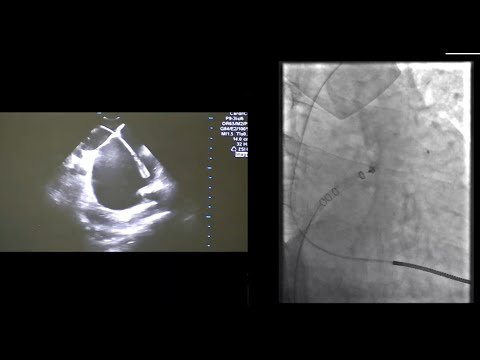

Left Atrial Appendage Closure by Watchman FLX and ICE